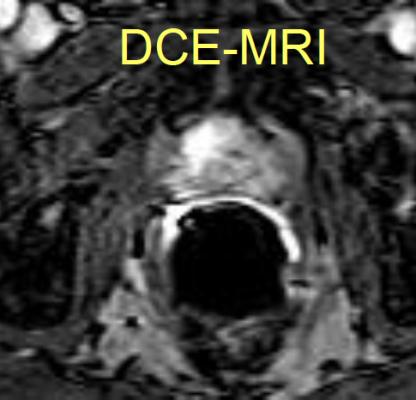

BPH is a condition in which the prostate is enlarged but not cancerous. Using an interventional radiology treatment known as prostate artery embolization (PAE), clinicians were able to improve patient symptoms, regardless of the size of BPH before the treatment, researchers found in a retrospective study.

In prostate artery embolization, a catheter is inserted into the femoral artery and guided to the prostate artery on both sides of the enlarged gland. Once positioned next to the prostate, microscopic spheres are delivered to block blood flow, causing the prostate to shrink. PAE is technically challenging, said Bagla. Interventional radiologists, given their knowledge of arterial anatomy, experience with microcatheter techniques and expertise in other embolization procedures, are the specialists best suited for the performance of PAE. He also noted that SIR supports the performance of high-quality clinical research to expand the numbers of patients studied, to extend the duration of follow-up and to compare the PAE procedure against existing surgical therapies.

Bagla and his team examined the cases of 78 patients who underwent prostate artery embolization for BPH as part of the clinicians' routine practice. Patients were categorized into three different analysis groups based on the size of the enlarged prostate: less than 50 cubic centimeters, between 50-80 cubic centimeters and greater than 80 cubic centimeters. The researchers evaluated the effectiveness of PAE in these patients at one, three and six months post-treatment.